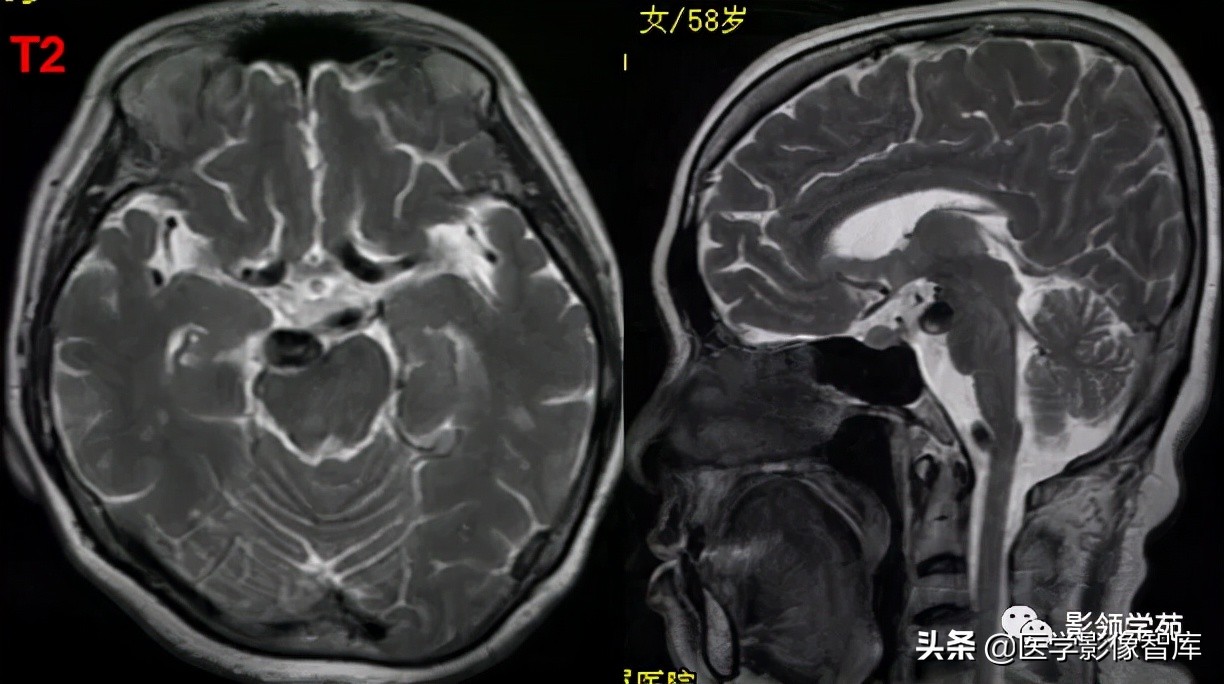

女 58岁,头晕、呕吐,桥脑右前方见一类圆形

高低混合(有血栓)T1及T2信号影,边界清楚、锐利。

明显不均匀强化(瘤内有血栓)。与基底动脉分界不清

头颅CTA:基底动脉起始部血管局部瘤样突起(宽基底),无占位效应。